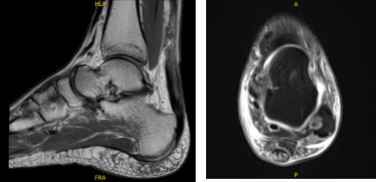

MRI was reviewed that showed full-thickness achilles tendon tear at the myotendinous junction 6 cm from the calcaneal insertion with a 4 cm gap retracted tendon stumps. Complete tear of the anterior talofibular ligament and calcaneofibular ligament. Diffuse lateral and posterior soft tissue edema.

MRI Left ankle non-contrast